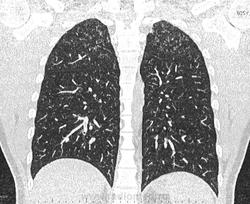

По jpeg впечатление очаговых изменений верхних долей и умеренного увеличения лимфоузлов средостения. Туберкулез на первое место.

Моё мнение то же самое, туберкулез. Добавила изображения.

Посев мокроты на туберкулез отрицательный. Пульмонолог по КТ ставит саркоидоз легких 2 степени. Какое Ваше мнение?

В диф. ряд на первое место предполагаю все же саркоидоз легких и ВГЛУ (по одной из классификаций 2 стадия, а не степень). В плане дальнейшего диагностического алгоритма: